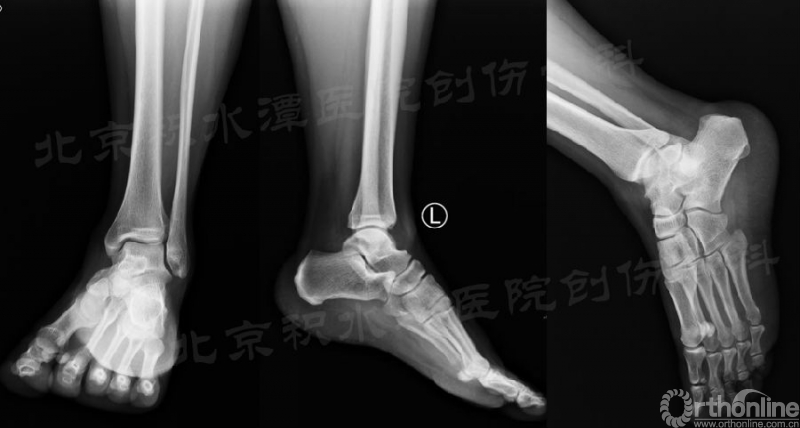

我们首先来看一例北京积水潭医院急诊室遇到的踝关节扭伤的病例。患者,女,43岁,急性病程,骑电动车停车时左足撑地时扭伤。既往左踝多次扭伤。

查体:坐轮椅于急诊就诊,左足不能负重。外踝肿胀,内踝无肿胀。外踝压痛,内踝无压痛;从内侧压后踝疼痛(内踝后缘外侧),从外侧压后踝轻微疼痛(Volkman结节)。

急诊常规拍摄X片:踝关节正侧位X线片无明显异常;但踝关节(或足)斜位可见后踝骨折无移位(不明显)。

复查CT可见后踝骨折无移位(猜测当时踝关节处于跖屈位,制动电动车使左踝受到轴向应力),胫腓骨正侧位带膝未见腓骨近端骨折。

对于以上这例病例,这种骨折类型也不是常见的踝关节骨折类型,若是没有很仔细的查体和阅片,很容易发生漏诊。